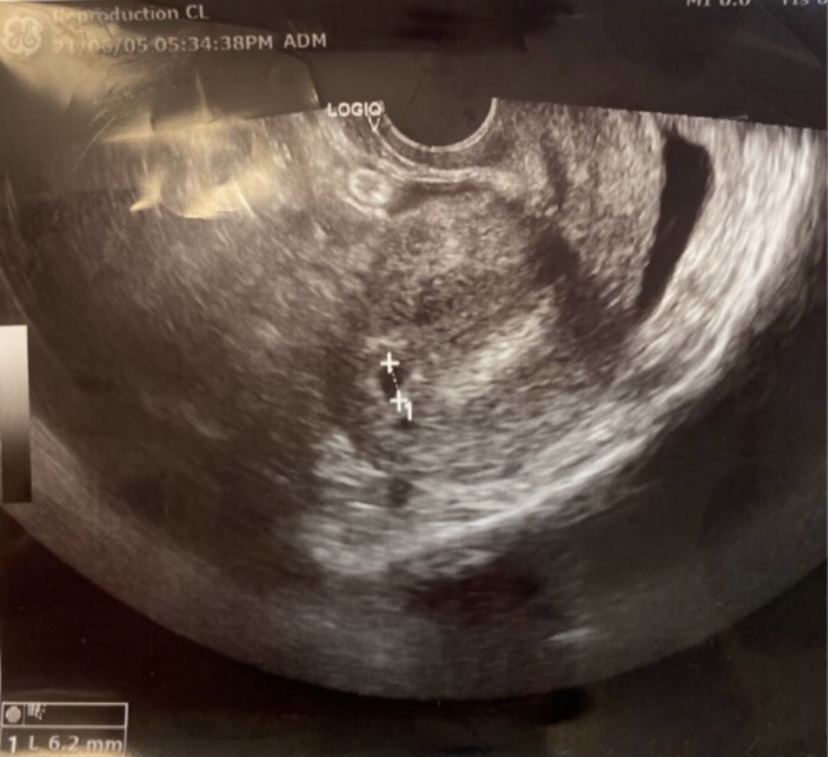

本日4w6dです胎嚢確認 6mm 出来ましたが卵巣が40mmに Yahoo 知恵袋